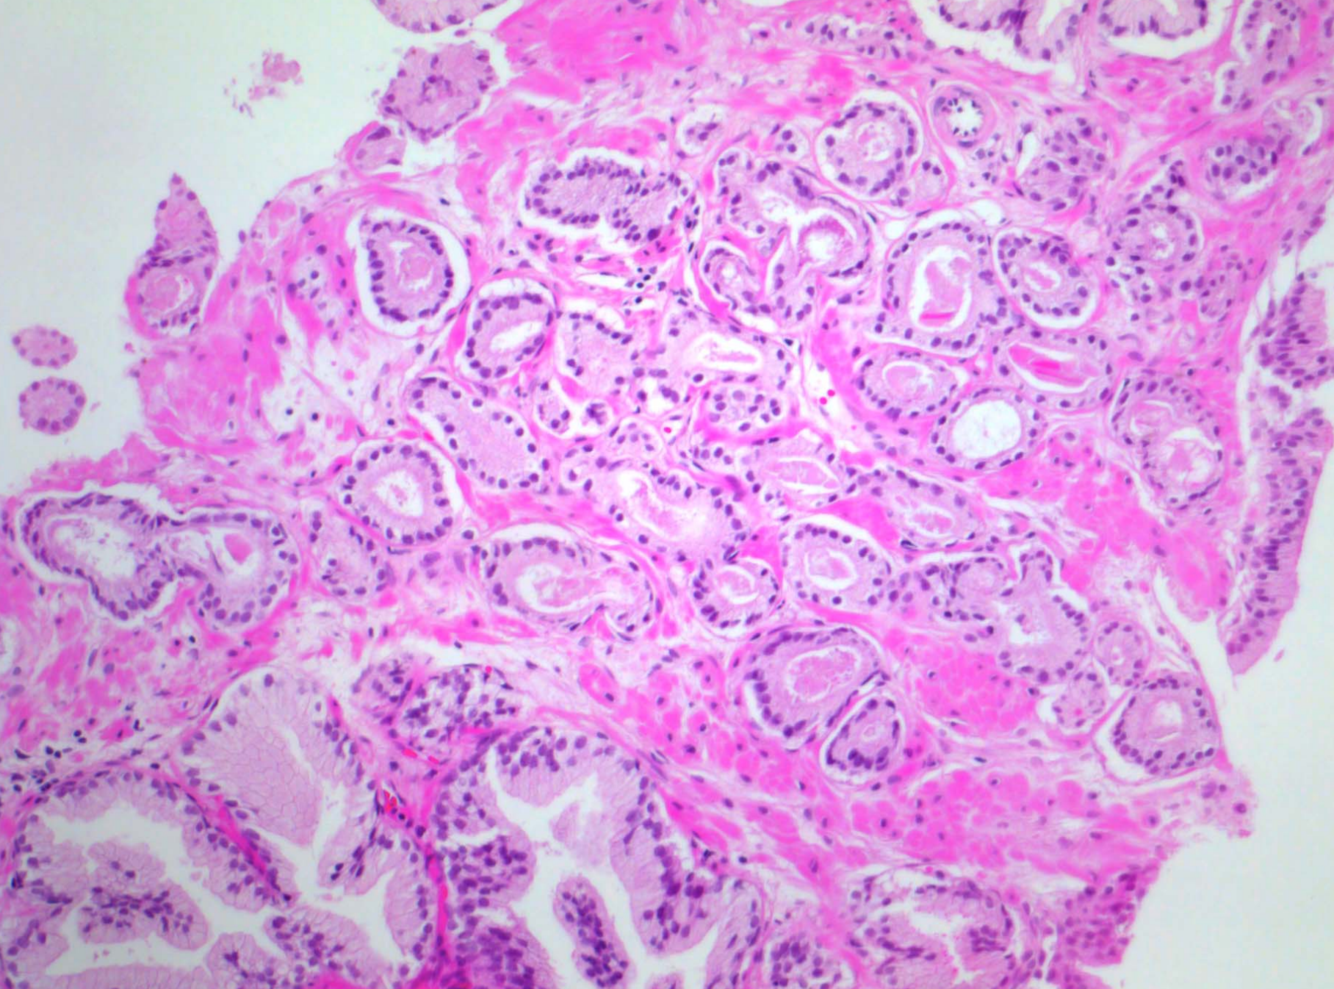

Welcher Tumortyp ist das?